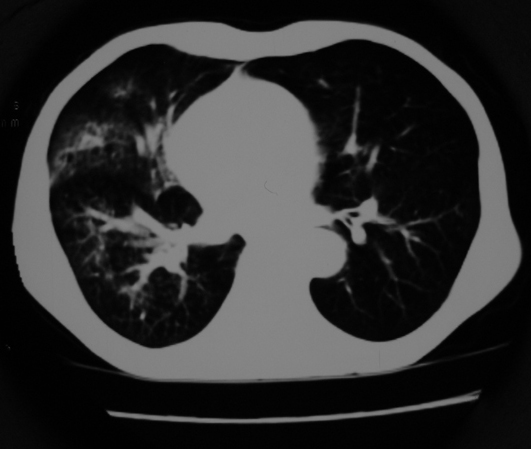

以下是引用同在2007-1-27 14:13:00的发言:[br]支持右侧中央型肺癌伴阻塞性病变.

以下是引用zjzjr在2007-1-27 16:56:00的发言:[br]支持右肺中心型肺癌伴阻塞性肺炎.